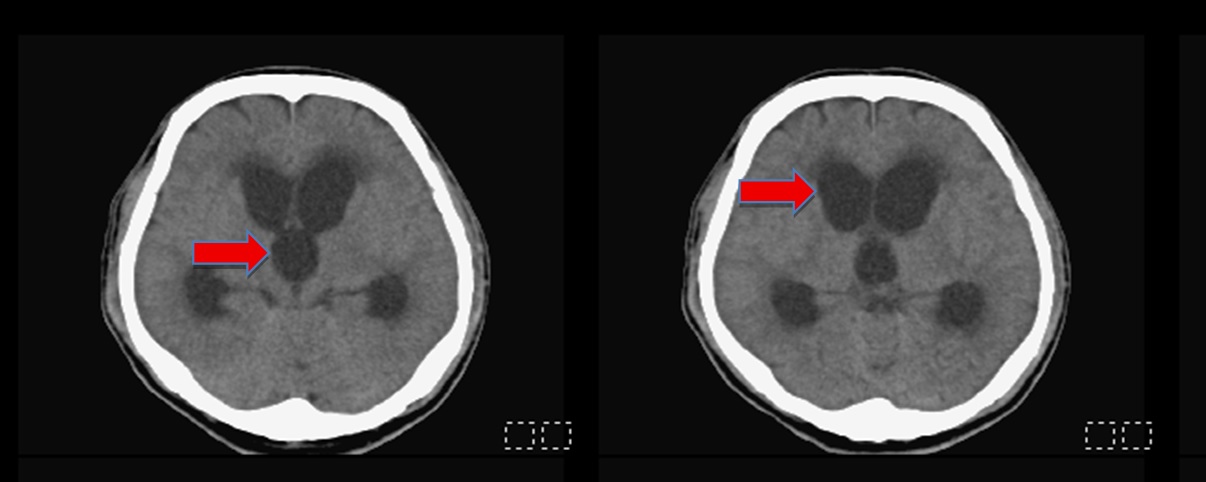

陳志豪醫師強調,早期辨識與介入治療是改善預後的關鍵,臨床可透過電腦斷層(CT)或磁振造影(MRI)影像學判斷及病程追蹤來評估是否需進行分流手術。從臨床經驗及研究都顯示,適時進行腦脊髓液分流手術可顯著提升病人的神經功能與生活品質。此個案則是手術後才恢復清楚意識及記憶,出院時感謝醫護團隊,自述「彷彿獲得重生」,術後半年追蹤原先腫大的腦室已恢復正常大小。